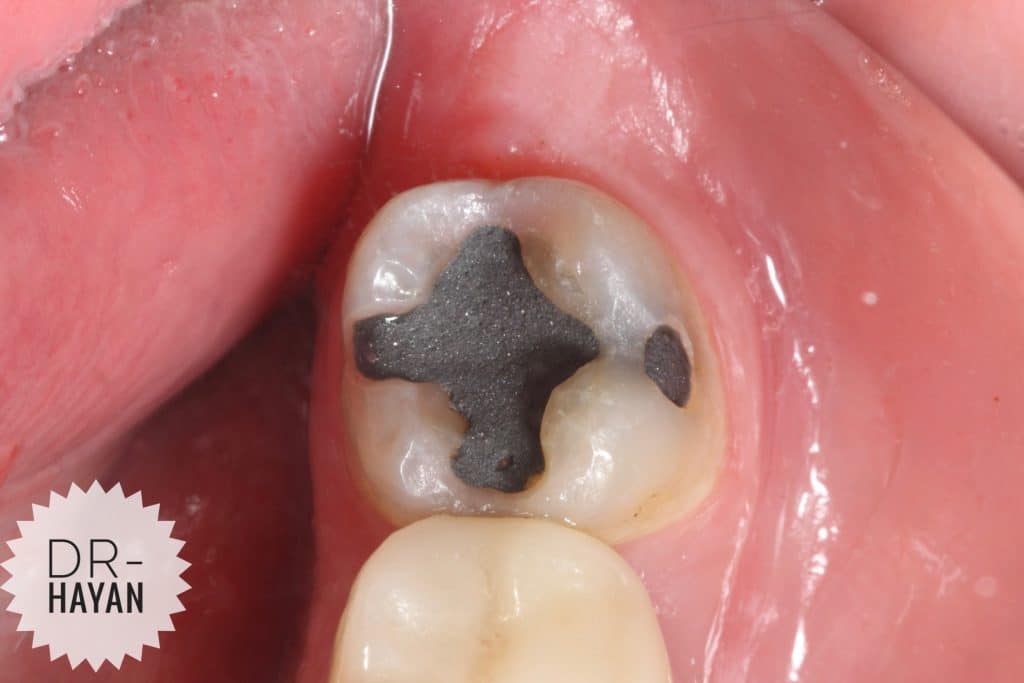

After remove the amalgam

As usual , recurrent caries under it